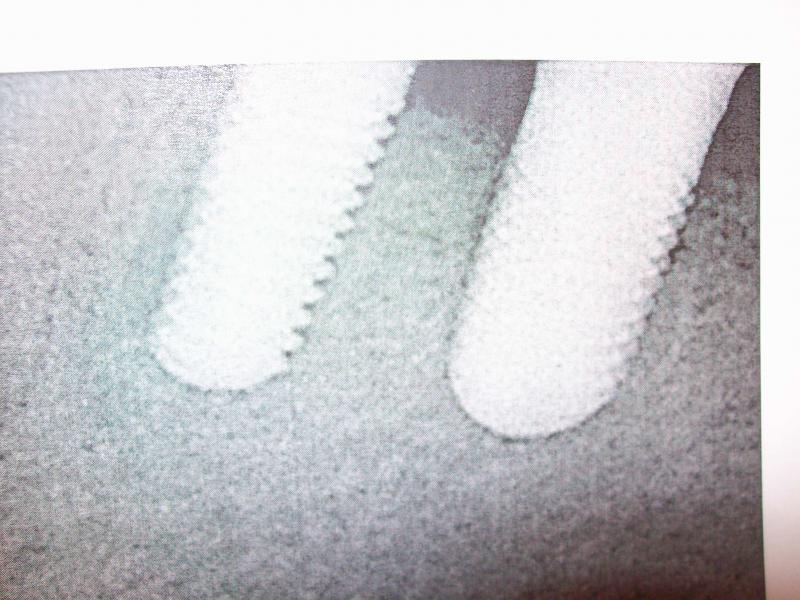

General Dentist,  Performs Root Canals ONLY - Microscope Trained Dentist

"DR. JET'S MISSION IS TO PERFORM  ROOT CANALS FOR A REDUCED FEE USING THE LATEST TECHNOLOGY  AND TECHNIQUES TO SERVICE THE MANY PEOPLE WHO ARE UNINSURED OR UNDER-INSURED GIVING EVERYONE AN OPPORTUNITY TO SAVE THEIR TOOTH!"